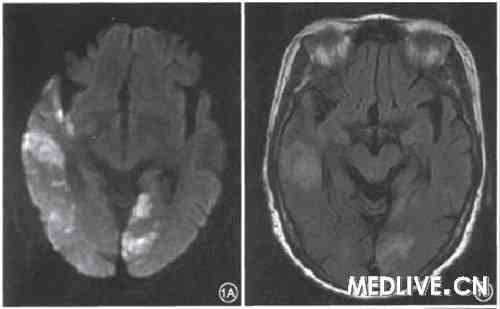

患者女,80岁,因双眼视力下降,伴头晕、头痛1周,于2009年1月15日前来就诊。既往诊断“正常眼压青光眼”2年。发现高血压、糖尿病1年。发病后首诊于眼科,视力双眼0.1,杯盘比:右眼0.7,左眼0.6,24 h眼压监测最高17 mmHg(1 mmHg=0.133 kPa),经过降眼压对症治疗后视力无改善,并逐渐出现左侧肢体无力。转诊神经内科。神经系统检查:神清、记忆力、定向力差。双侧瞳孔小,直径约2 mm,对光反射存在。眼球各向活动正常,余颅神经检查未见异常。左侧肢体轻瘫试验阳性,双侧Babinski征阴性。头颅MRI显示双侧枕叶、右侧颞叶DWl高信号(图1),提示新鲜梗死灶。诊断为多发性脑梗死、皮质盲。

图1皮质肓患者头颅MRI弥散加权轴位扫描。1A示双侧枕叶(左侧显著)、

右侧颞叶片状高信号,lB示Flair加权相应部位亦为高信号,提示急性期脑梗死